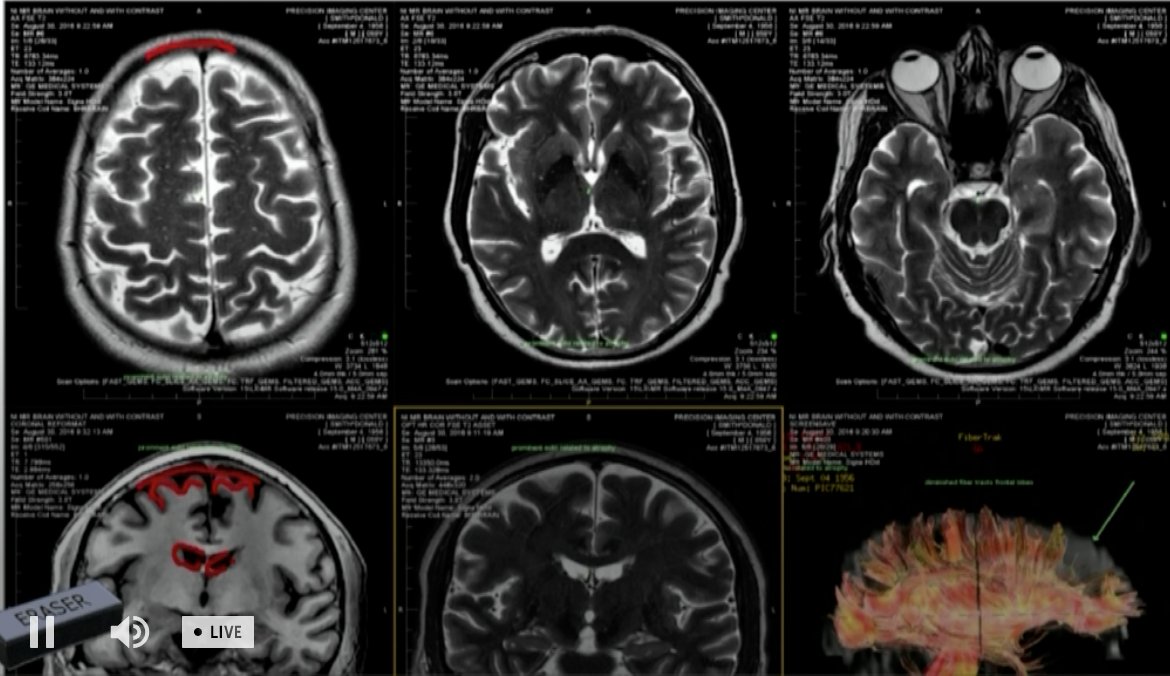

Dr Geoff Colino met with #DonaldSmith April 6 at the jail. He's a neurologist who conducted a history and physical & analyzed Smith's MRI brain scans @FCN2go

#DonaldSmith MRI scans being discussed @FCN2go